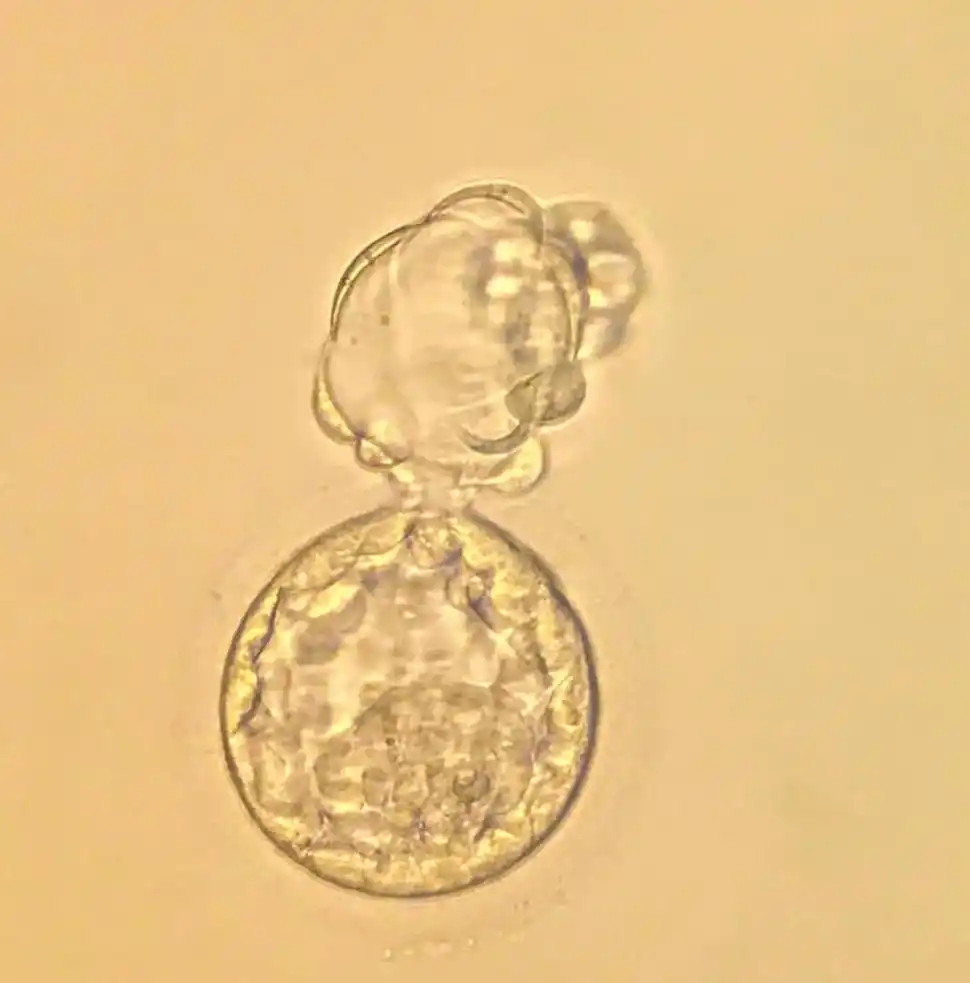

1 Ovocito inicial recién donado.

3. Embrión en el quinto día.

3. Embrión a 6 eclosionando

2. Embrión en el tercer día de vida.